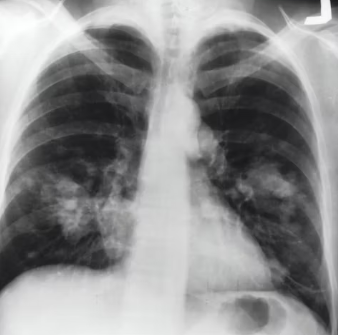

천식 진단에 있어 가장 핵심적인 검사는 폐기능 검사(Spirometry)입니다. 폐기능 검사를 통해 기관지 협착 유무를 확인하고, 특히 기관지확장제 흡입 후 반응(가역성)을 평가하여 천식을 진단합니다. 청소년 및 성인 천식 진단 시, 기관지 확장제 투여 후 FEV1(1초간 강제 날숨량)이 12% 이상, 그리고 200mL 이상 증가하면 가역성을 확인하여 천식을 진단할 수 있습니다.

이 외에 메타콜린 기관지 유발 검사로 기관지 과민성을 확인하며, 알레르기 피부 반응 검사나 혈액 검사(특이 IgE 항체)를 통해 알레르겐을 파악하기도 합니다. 의료진은 이러한 검사 결과를 종합하여 천식의 진단과 중증도를 판단합니다.

의료진은 임상 증상, 폐기능 검사 결과, 그리고 기관지확장제 반응을 종합하여 천식을 진단합니다. 이때 만성폐쇄성 폐질환(COPD), 기관지 확장증, 만성 기관지염, 위식도 역류 질환 등 유사한 호흡기 증상을 유발하는 다른 질환들과의 정확한 감별 진단을 내리는 것이 매우 중요합니다.